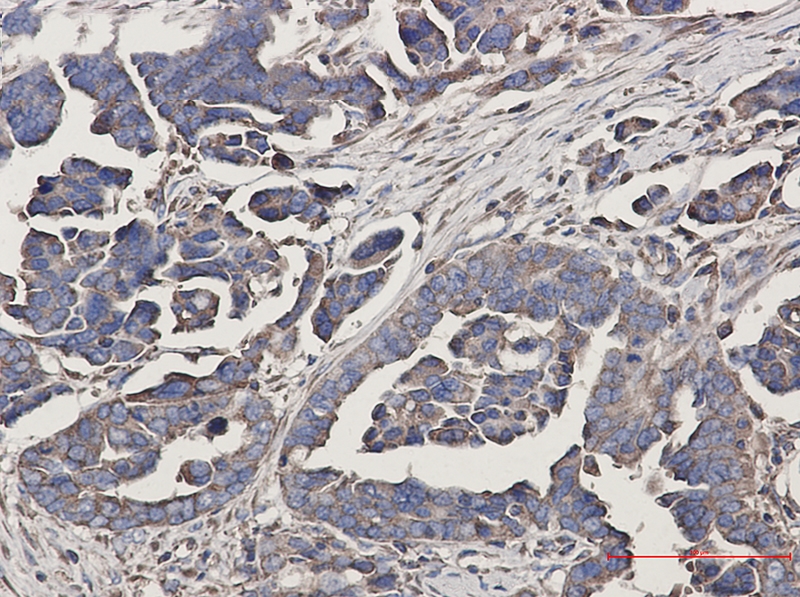

Immunohistochemistry of WDR1 in paraffin-embedded Human Cholangiocarcinoma using WDR1 Rabbit mAb at dilution 1/50